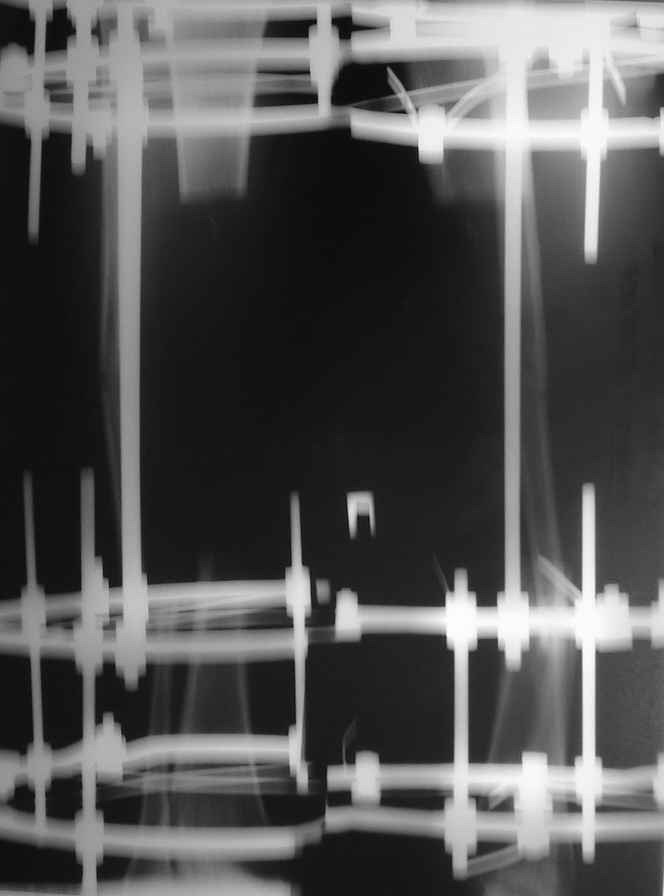

В приложении рентгенограмма через год после операции.